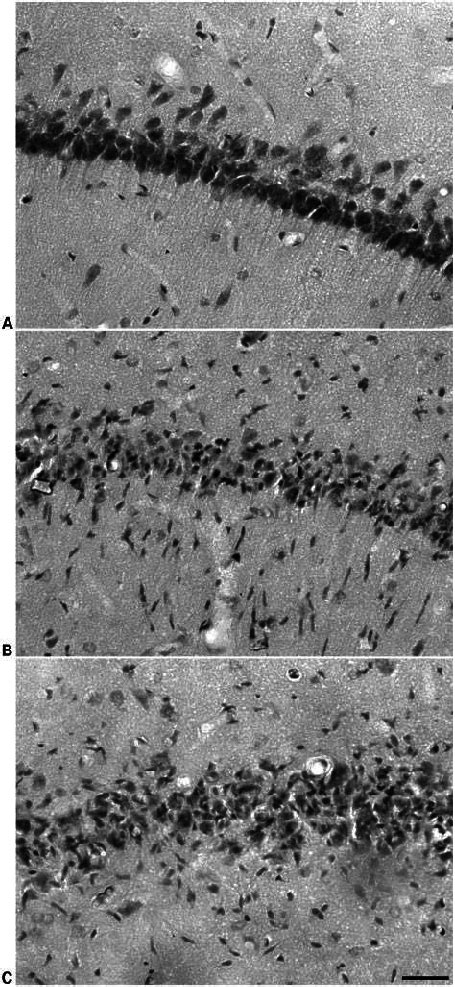

• Pathological Morphology Of Hippocampal Ca1 Region Of Rats In Each ...

• The Neuropathological Evaluation On The Hippocampal Ca1 Region Of Rats ...

• Histopathological Changes In The Hippocampal Ca1 Of Rats Treated ...

• -histological Sections Of The Hippocampal Ca1 Region Of Rats | Download ...